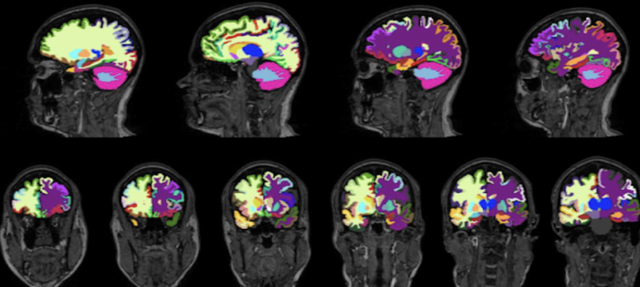

脑区体积也采用了深度学习方法测量,使用FastSurfer卷积神经网络,分割了96个不同的大脑区域。

△脑体积分割结果

考虑到不同参与者头部大小的差异,研究人员还使用了一个单独的深度学习模型来分割颅内容积。

他们手动标注了60名参与者的颅内隔室(头颅内的一系列脑室),然后用这些数据训练医学图像分析深度学习框架nnUNet,用于生成颅内掩膜(覆盖在颅骨内部,包围和保护中枢神经系统的三层薄膜)。